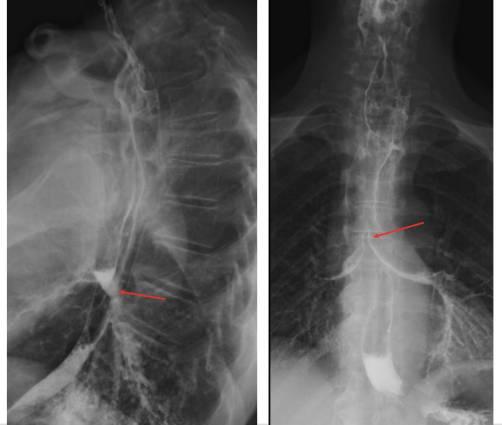

从第一次手术开始,住院患者的整体康复经过了8个月的时间。住院包括言语和语言治疗、营养师、物理治疗和咨询团队。第二阶段手术后12天,CT扫描和钡剂造影检查发现咽胃吻合口没有泄漏(图6)。在出院前,随着经皮空肠造口术,经口摄入逐渐增加。门诊复查显示,患者正在进食不同浓度的食物,体重和体力增加,使用电子喉咽装置发声。

图6 术后放射学图像。CT扫描(左)显示重建的胃管胸骨后通道。吞钡(右)显示咽胃上吻合口无泄漏